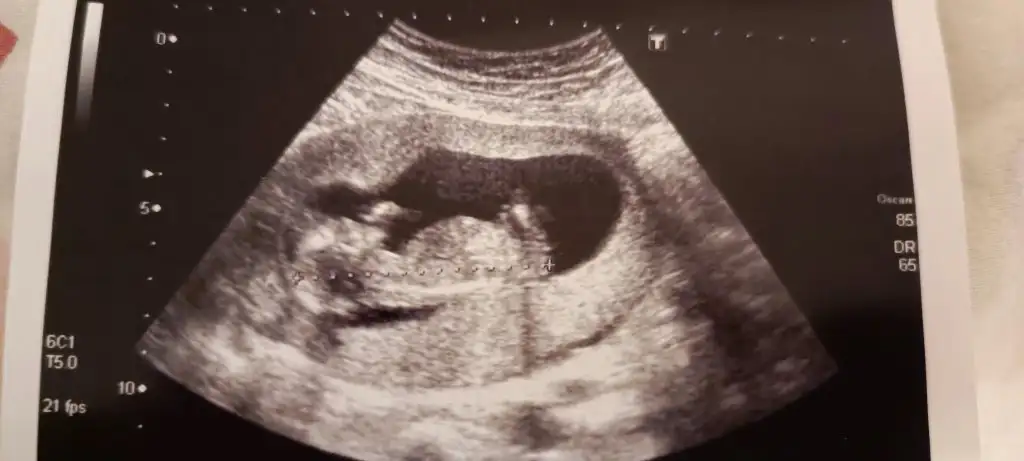

Erkek :)Eki Görüntüle 3211659

Tahminde bulunabilen varmı kızlar 12+3